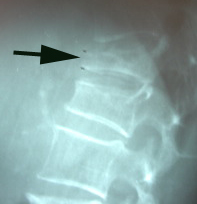

Fortunately it is a rare occurrence, but pregnancy- and lactation-associated osteoporosis can happen. Aurora Chiropractic Center closely watches our Juneau pregnant patients or women in postpartum period to see if they acquire continuous back pain, especially if they have risk factors or secondary causes of osteoporosis. What comes of pregnancy-associated-osteoporosis? Vertebral fractures. (1)

Don’t be too alarmed by vertebral fractures as a result of pregnancy associated osteoporosis as a new case report gives hope. A woman with seven vertebral compression fractures was treated conservatively with strontium ranelate and supplementation of calcium and cholecalciferol. (2) 7 fractures! Wow. This treatment combination quickly restored the bone mineral density value in this case. Imagine if you have just one fracture!

Vertebral fractures as a result of osteoporosis - pregnancy-associated or lactation-related or genetically-linked - are not to be taken lightly. Aurora Chiropractic Center is the chiropractic healthcare provider to trust to find and/or manage their healing. So if you are pregnant and experience back pain, contact Aurora Chiropractic Center. You will be examined carefully and treated gently. Our other Juneau pregnant ladies so appreciate the gentle stretching we can achieve with Cox Technic, even in the later months of pregnancy. If you are pregnant and have a family history of osteoporosis, contact Aurora Chiropractic Center for some advice to protect against its effects. Exercise, nutrition, and chiropractic treatment may be part of the treatment plan.